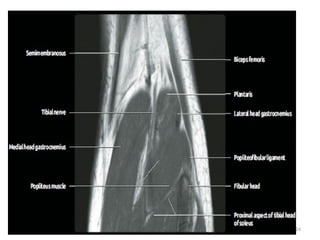

Tibial Nerve

• Largest division of sciatic nerve.

• Arises from ventral surface of sacral plexus(L4-S3) and runs

medially.

• Courses through the popliteal fossa passing deep to

gastrocnemius muscle.

04/29/2025 22

• It passes inferiorly between the heads of gastrocnemius and

deep to soleus muscle.

• Continues inferiorly in the midline deep to soleus and

superficial to the tibialis posterior muscle.

• At the ankle passes under flexor retinaculum in the tarsal

tunnel.